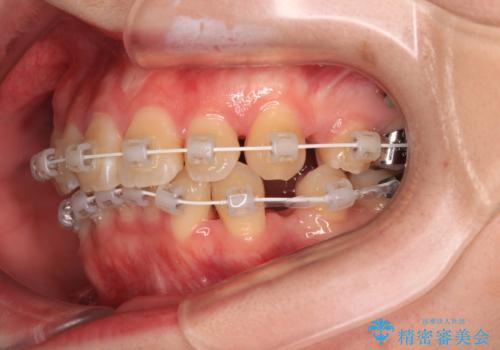

- 矯正装置

- 審美装置

- 上下前歯のデコボコを気にして来院された患者様です。

口元の突出感はあまりなかったものの、デコボコを非抜歯で改善すると出っ歯になる可能性があるため、上下左右の第一小臼歯4本を抜歯し、ワイヤー装置にて矯正治療を行うこととしました。

口元の突出感はなかったものの、捻転や八重歯を改善するために補助装置を併用する必要がありました。

予定の2年半を越えてしまいましたが、無事にきれいな口元に仕上げることができました。